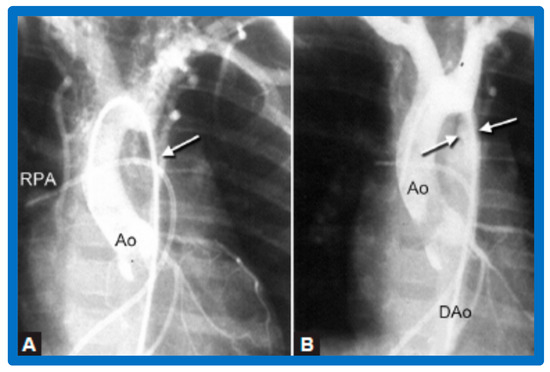

3.3. Aortic Coarctation, Native

4.3. Aortic Coarctation–Native

Revisit BA in the Neonate and Young Infant